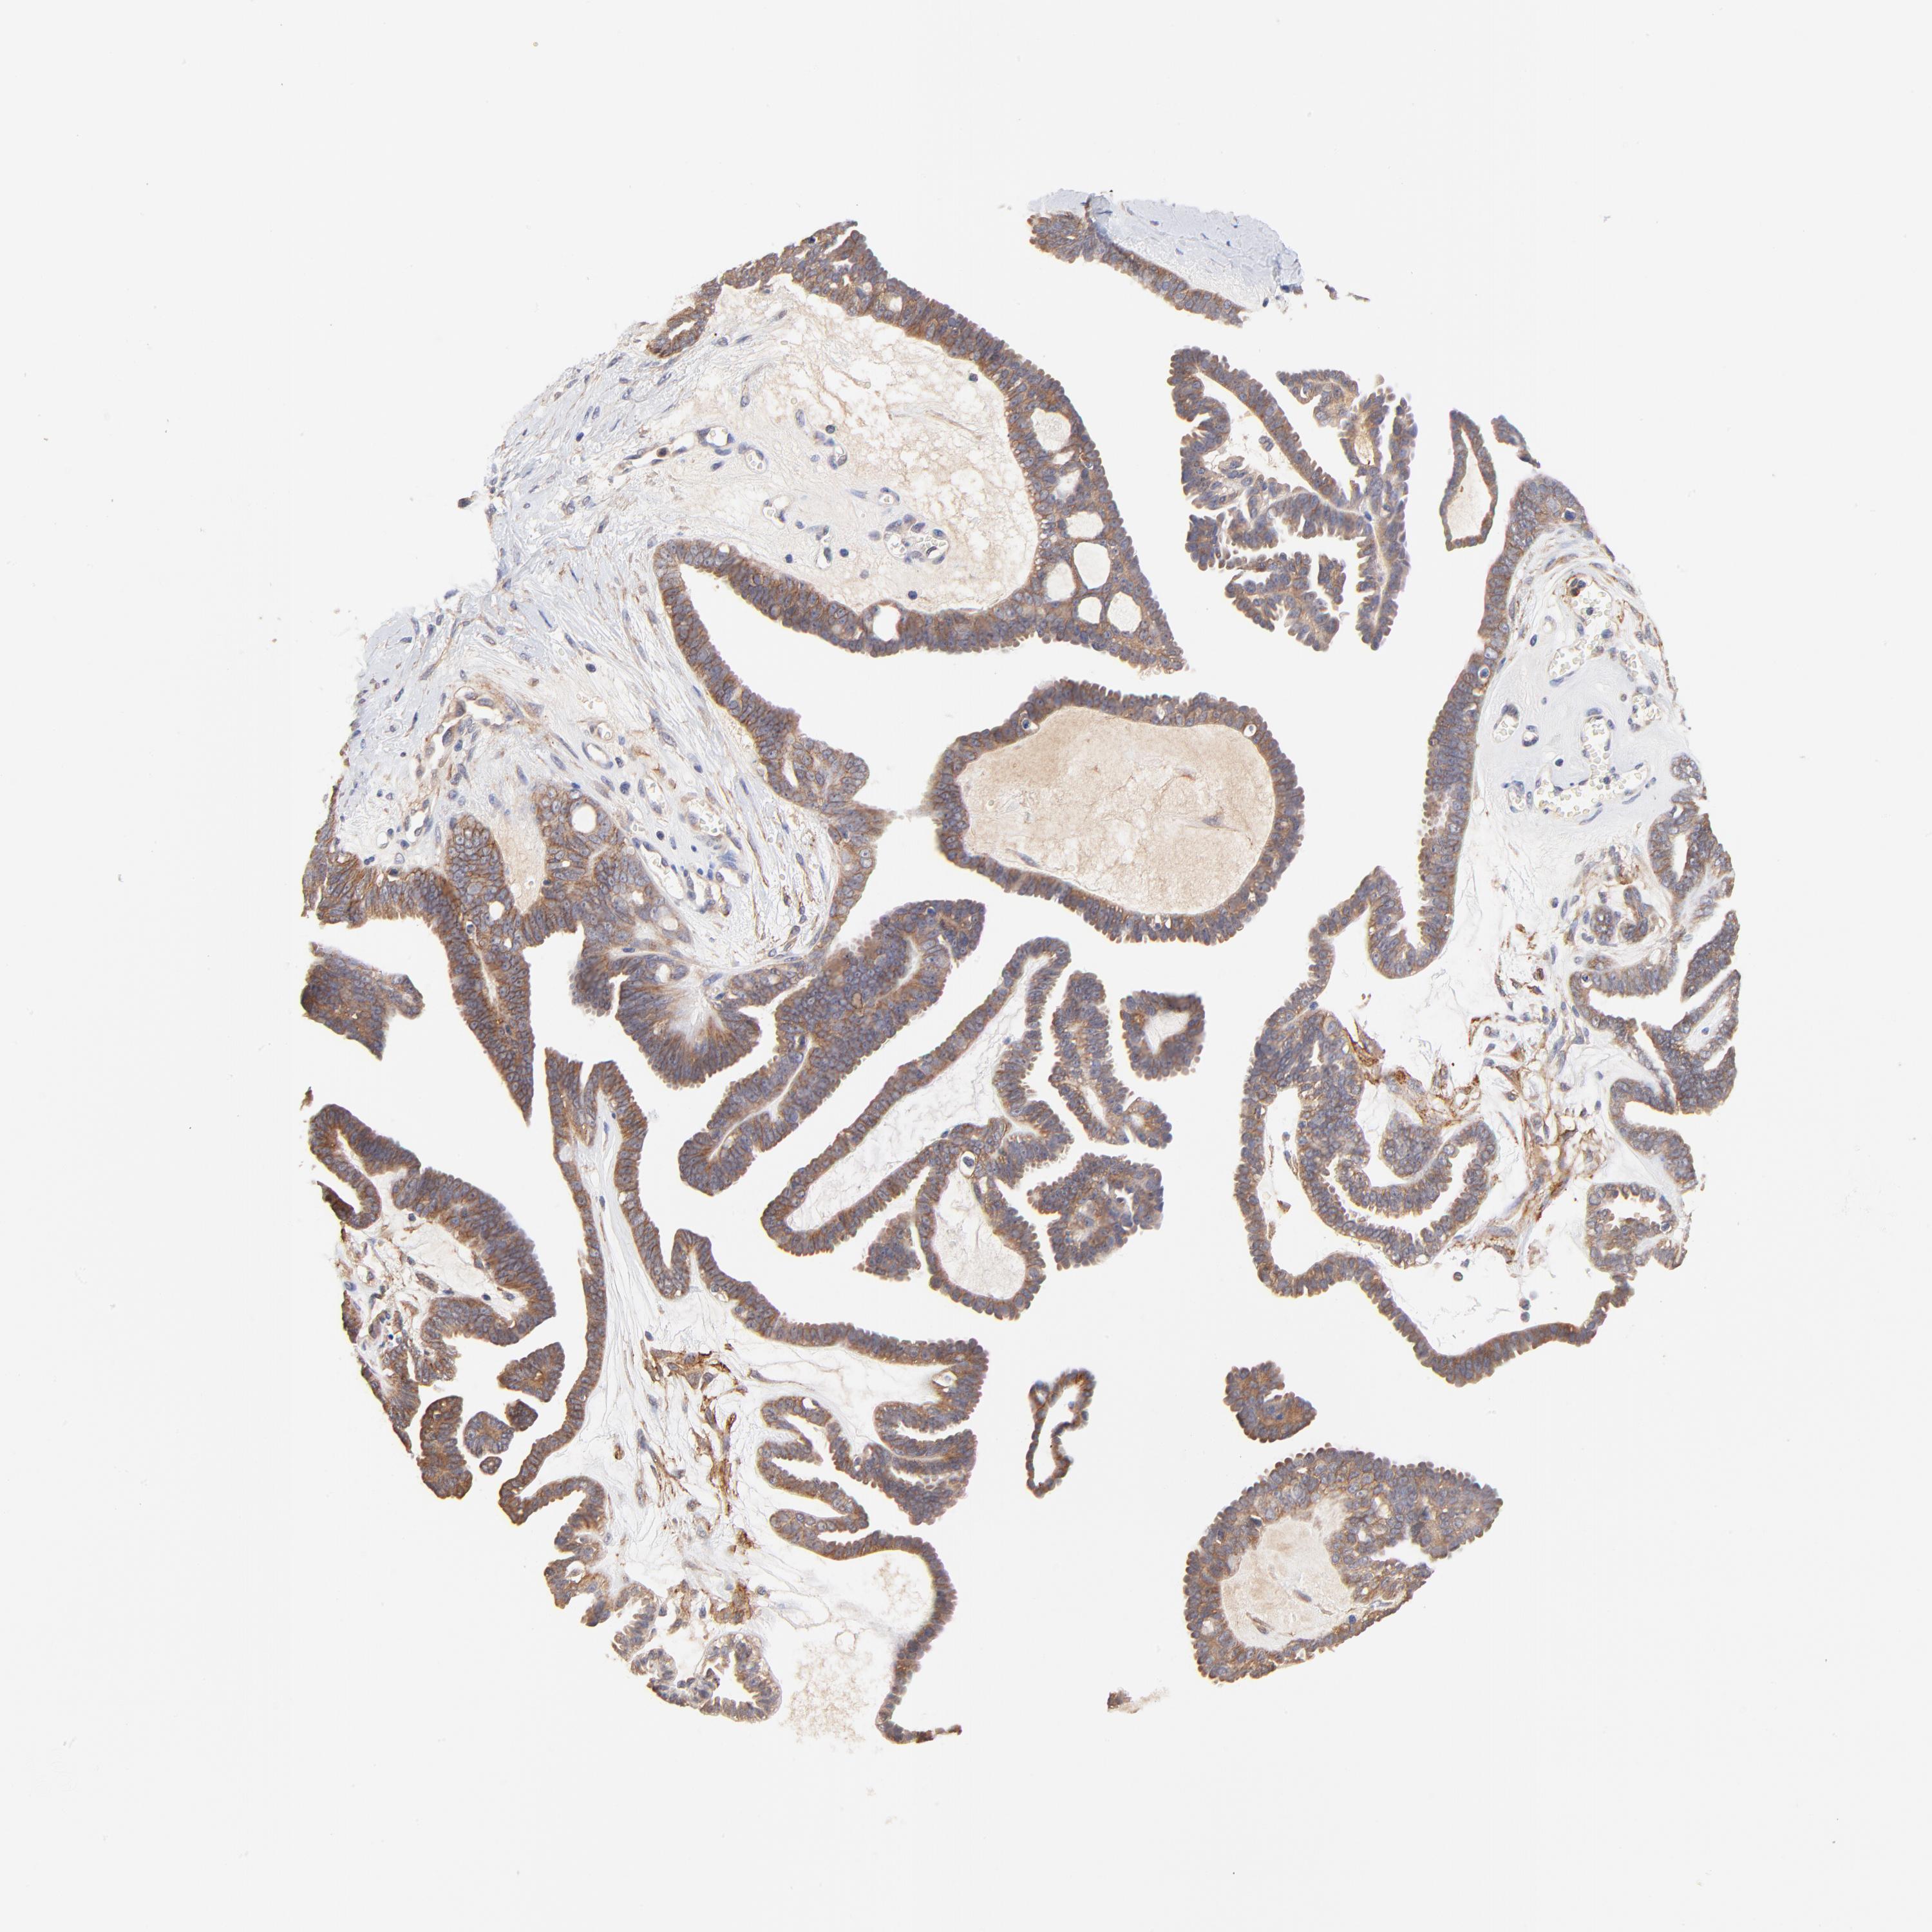

OVARIAN CANCER - Protein expressioni

A mouse-over function shows sample information and annotation data. Click on an image to view it in a full screen mode. Samples can be filtered based on level of antibody staining by selecting one or several of the following categories: high, medium, low and not detected. The assay and annotation is described here.

Note that samples used for immunohistochemistry by the Human Protein Atlas do not correspond to samples in the TCGA dataset.

Antibody stainingi

Antibody staining in the annotated cell types in the current human tissue is reported as not detected, low, medium, or high, based on conventional immunohistochemistry profiling in selected tissues. This score is based on the combination of the staining intensity and fraction of stained cells.

Each image is clickable and will lead to virtual microscopy that enables deeper exploration of all samples and also displays staining intensity scores, fraction scores and subcellular localization as well as patient and tissue information for each sample.

Antibody HPA003222

Staining

High

Medium

Low

Not detected

Intensity

Strong

Moderate

Weak

Negative

Quantity

>75%

75%-25%

<25%

None

Location

Nuclear

Cytoplasmic/membranous

Cytoplasmic/membranous,nuclear

Carcinoma, endometroid

Cystadenocarcinoma, serous, NOS

Cystadenocarcinoma, mucinous, NOS